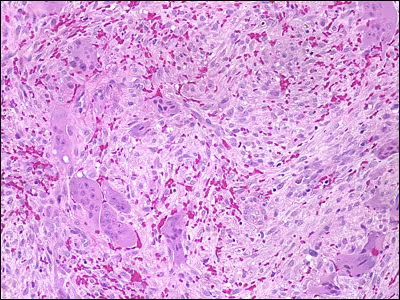

Microscopic examination revealed fragmented specimens composed predominantly of soft tissue. Small spicules of vital bone were scattered within the tissue and likely represented the speckled white material seen at surgery. The soft tissue consisted of a background stroma of proliferating spindle-shaped fibroblastic appearing cells (Figure 7).

Embedded within the stroma, scattered multinucleated giant cells were appreciated (Figures 7 and 8).

Figure 7. Histologic features demonstrating fibrous connective tissue stroma with proliferating spindle-shaped cells and focal aggregates of multinucleated giant cells (10x).

Figure 8. Histologic features demonstrating focal aggregates of multinucleated giant cells (20x).